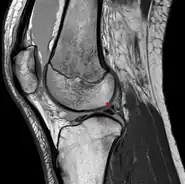

Posterior meniscofemoral ligament on MRI, sagittal

The Posterior meniscofemoral ligament (also known as the ligament of Wrisberg) is a small fibrous band of the knee joint. It attaches to the posterior area of the lateral meniscus and crosses superiorly and medially behind the posterior cruciate ligament to attach to the medial condyle of the femur.[1]

The posterior meniscofemoral ligament is found in 64.4% of the subjects in MRI scan of the knee.[1]